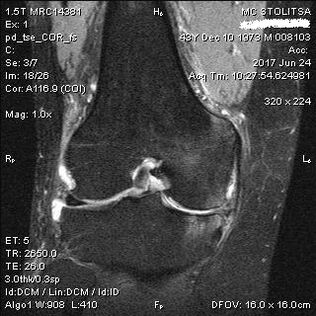

The diagnosis of arthrosis of the knee joint is made in the rheumatologist's or orthopedist's office.The doctor examines the affected joint, palpates it, listens to complaints and asks additional questions.He performs several tests - for example, asking the patient to bend his leg or walk a few steps.Then, if it is necessary to clarify the stage of the disease or the nature of pathological changes, he will refer you for additional studies.For example, for a CT or X-ray.